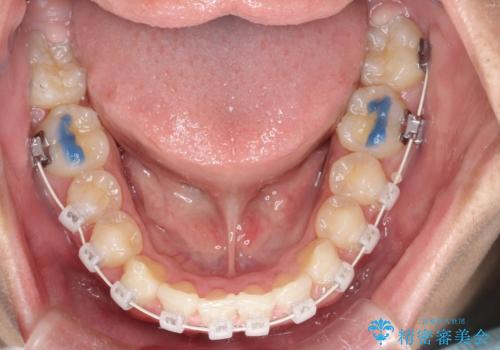

八重歯・歯並びのデコボコとディープバイトを改善した抜歯ワイヤー矯正症例

- ワイヤー(審美装置)

矯正の精密検査の結果上顎左右4番の計2本を抜歯し、審美性に配慮したワイヤー矯正装置(審美装置)を用いて治療を行いました。

八重歯などの歯列のデコボコが綺麗に改善され、患者様にも大変喜んでいただけました。また、咬み合わせが深い「ディープバイト」も併せて改善し、見た目だけでなく機能面でもバランスの取れた咬合を獲得しています。